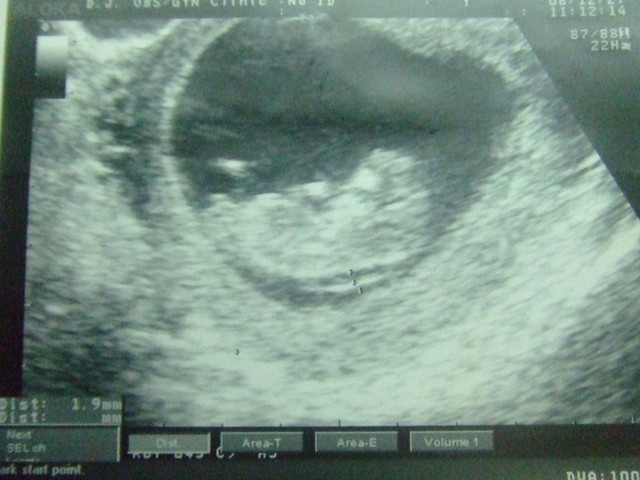

今天身長38.8mm~

頭頭就佔掉快一半了耶~

隱約可見眼睛和下巴~

有人形出現囉!!

但還是有點像外星人~^^"

但有點讓人擔心的是你的頸後透明帶有點寬~